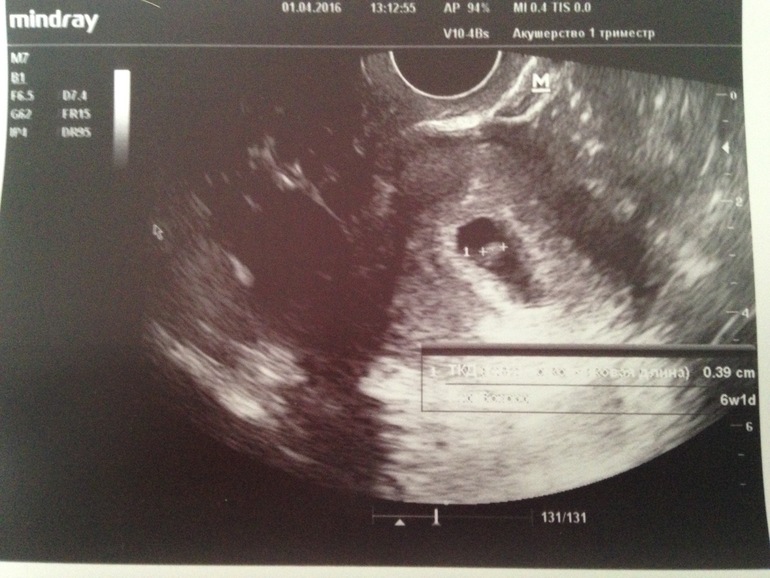

Узи в 6 недель и 1 день

У нас получилось! Я беременна!Сходила сегодня на узи, нам сегодня 6 акушерских неделек и 1 день. Долго думала идти или нет. Но пугали переодические достаточно ощутимые боли, но как оказалось зря. Очень хороший попался врач, все объяснил, рассказал и показал. Бусинка в матке, все хорошо, тонуса нет. Показали как бьется сердечко, 107 в минуту. КТР 3,9. Желтое тело в левом яичнике, вот его и тянуло по началу у меня. Теперь вот думаю когда родителям то рассказывать, сейчас или подождать ещё. А то знаю только я и муж, а иногда так хочется с кем то посоветоваться.